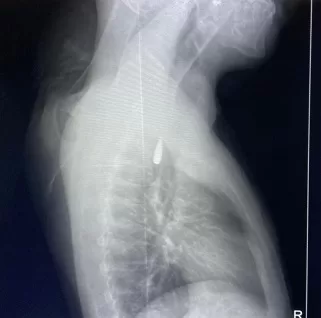

الذي كان قد تعرض لإصابة بطلق ناري في الرأس منذ فترة إستقر المقذوف على إثرها داخل تجويف القفص الصدري قرب الشريان الأورطي وهو أكبر وأهم شرايين الجسم والمسؤول عن تغذية جميع الأعضاء الحيوية

فيما كشف الدكتور تامر عبد الله عميد كلية الطب ورئيس مجلس إدارة المستشفيات الجامعية أن الفريق الطبي نجح في إستخراج المقذوف بأمان بعد عملية جراحية نادرة إستمرت عدة ساعات داخل المستشفى الجامعي الجديد حيث خضع المريض بعدها للرعاية الطبية اللازمة وحالته حاليًا مستقرة وتحت المتابعة الدقيقة من الفريق المختص